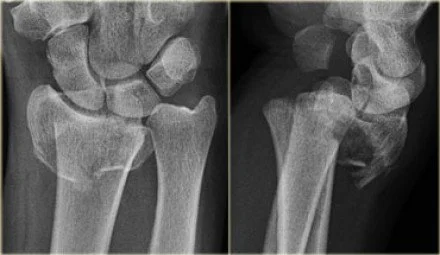

Frequently quoted to be the second most common fracture, a distal radius fracture is by far the most common fracture I see in the ED (maybe all those clavicle fractures get seen in the PCP's office). This fracture comes in many types depending on the mechanism and age (i.e. fragility) of the patient. Common types include: Colles', Smith's, dorsal and volar angulated Barton's (line one below), Die-punch, Chauffeur's, and ulnar styloid (line two plus an impacted intra-artciular comminuted distal radius and ulna styloid fracture) to name a few.  And this is excluding the common pediatric greenstick or torus fractures. Of course, any fracture should be described thoroughly as intra or extra-articular, angulated, impacted, and/or displaced. All of the following images are form The Radiology Assistant and while in a little more depth than you may need, I think it is worth a read.

Most wrist injuries are going to come in after a FOOSH. Obviously all the above fractures are named after their radiographic findings so you will not miss them, but you can miss a particularly dangerous fracture, the occult scaphoid (aka navicular) fracture, because it does, by definition, not show up plain films. Therefore, you must press on the anatomic snuffbox of every patient after a FOOSH (I document this on every fall even without wrist pain).